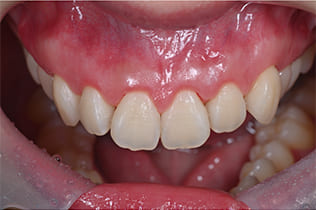

Case01

- 原因

- ガミースマイル

- 治療回数

- 1回

- 治療期間

- 術後治癒も含めて約1か月

- 治療内容

- ガミースマイル改善治療

- 治療費用

- 121,000円

(1ブロックあたり、6前歯部分)

笑った時に歯茎が見えてしまうガミースマイルを改善したいとのことでご来院された患者様です。術後も大変満足していただきました。